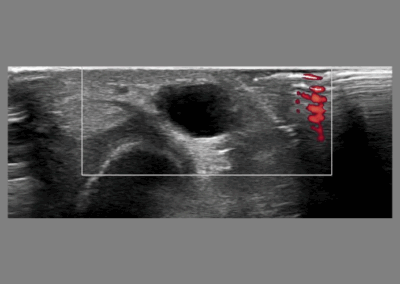

Depending on individual needs, imaging is available as part of the initial investigation. These include MRI, X-rays, CT and Ultrasound scans. Consultations are available to discuss this further.